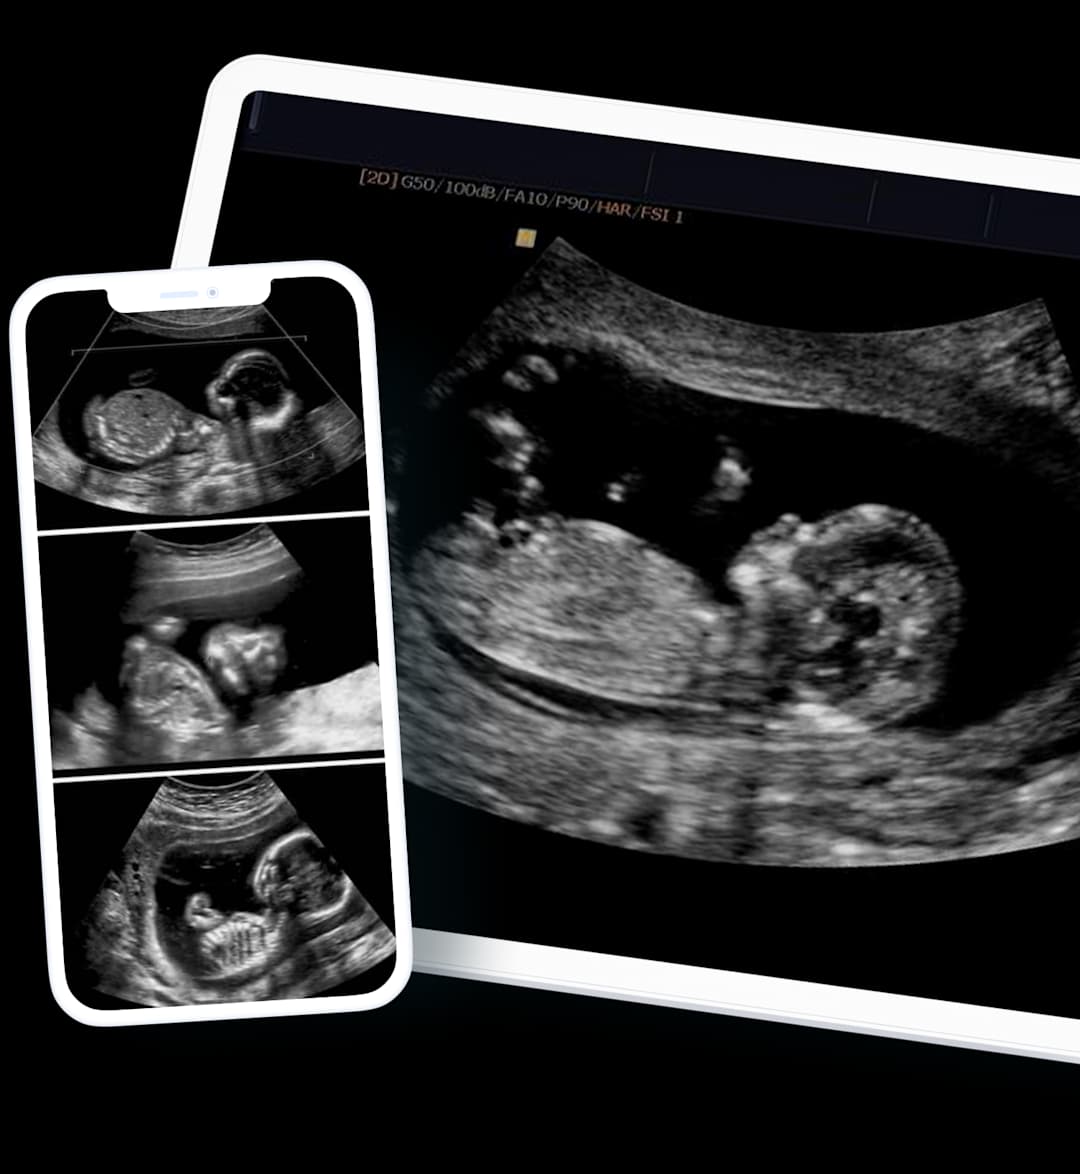

Anomaly Scan / Anatomy Scan: What should you expect?

Pregnancy is a journey filled with moments of joy and anticipation, and the anomaly scan—or anatomy scan—is a significant and exciting milestone. This article will guide you through what an anomaly scan is, what to expect during the procedure, the findings you might encounter, and how to interpret the results.